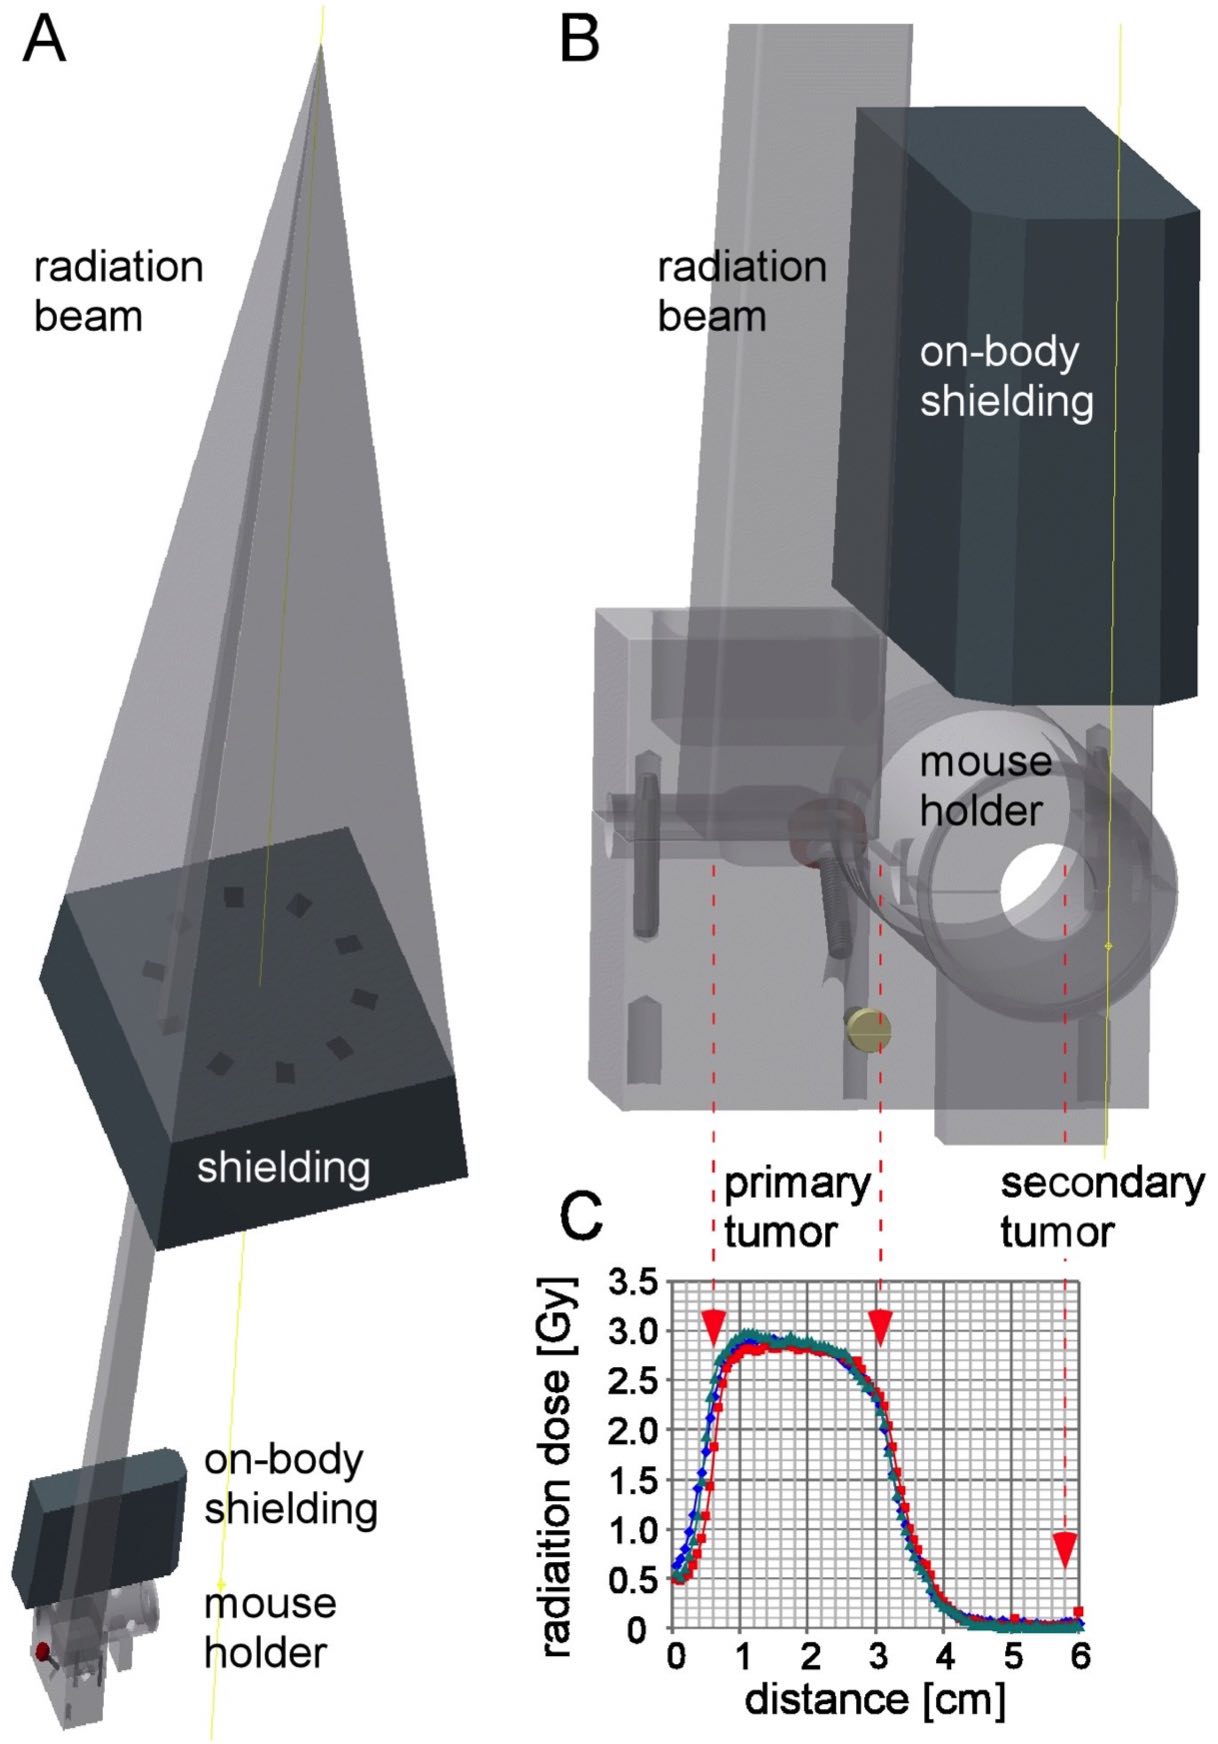

Anecdotal clinical reports suggest that local tumor irradiation alone may also exert systemic or abscopal anti-tumor immune effects with subsequent control of non-irradiated metastases. This study used a syngeneic mouse model with a primary irradiated and a secondary non-irradiated tumor to study abscopal effects of local radiotherapy combined with RNActive® vaccination.